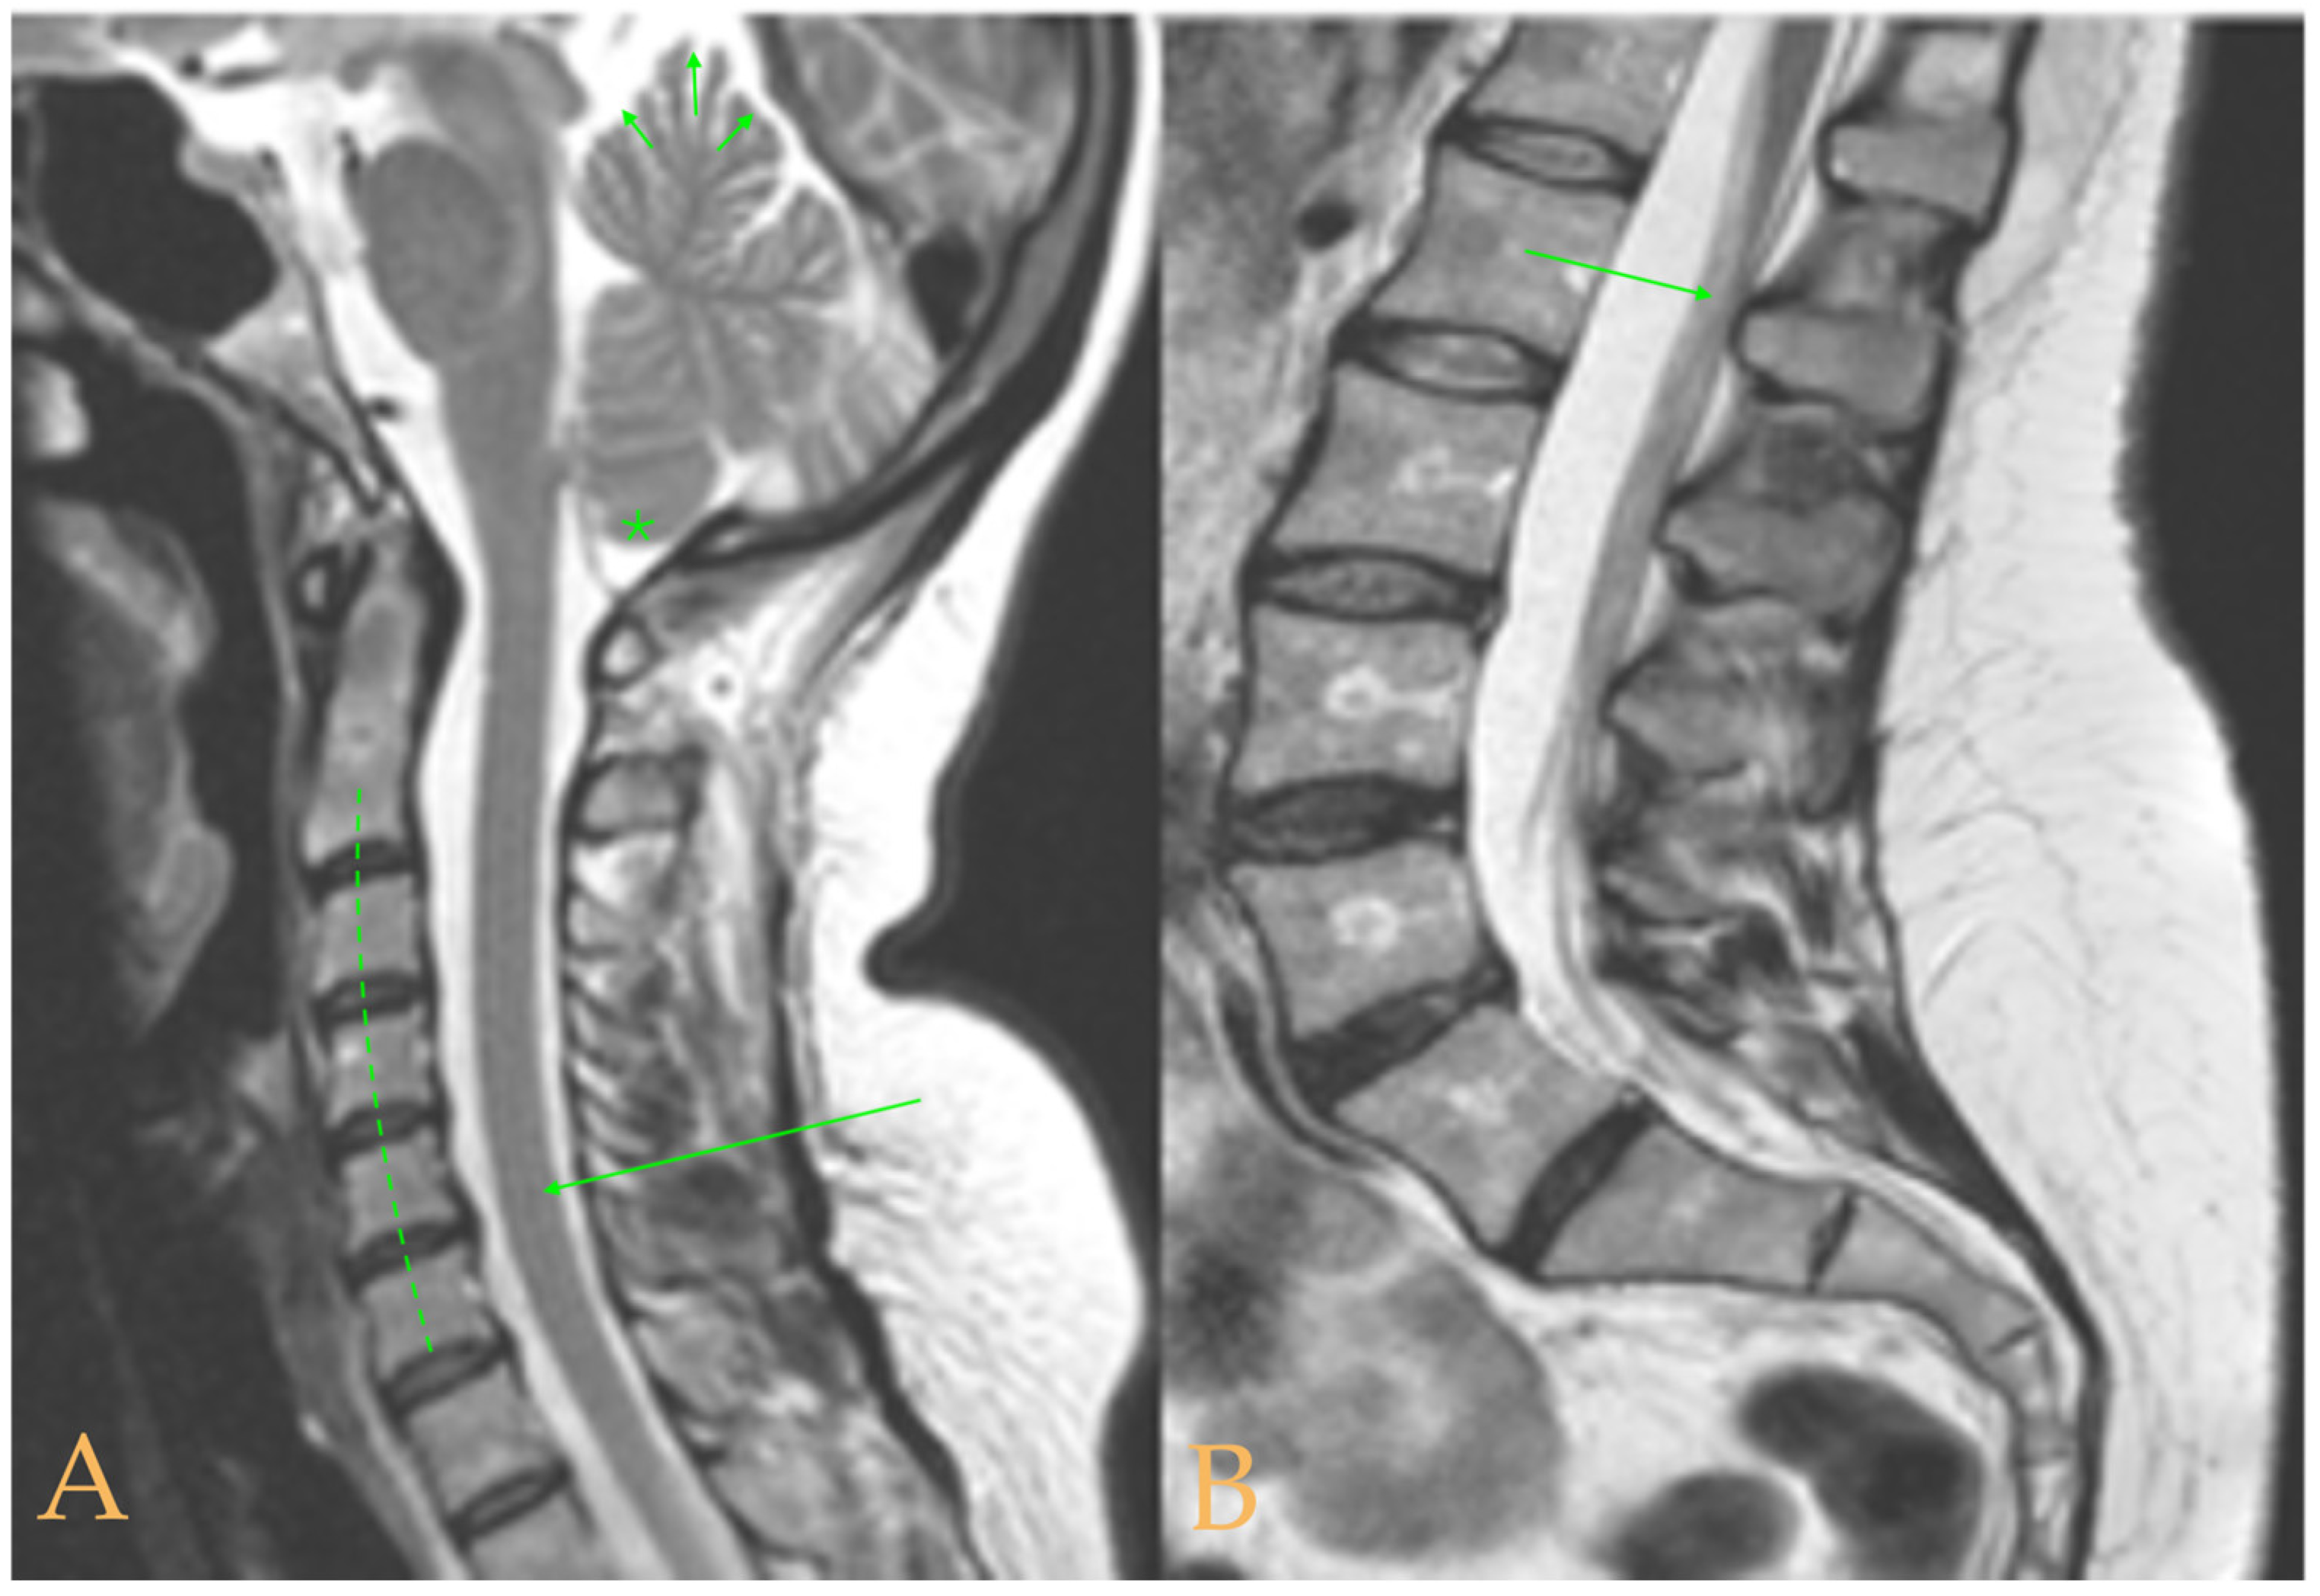

The MRI showed a descent of the cerebellar tonsils, increased supracerebral space, and micro lacunae in the bilateral white matter and the left basal ganglia. Upper cervical kyphosis and straightening in the lower levels. Surgical arthrodesis at C4-C5 and C5-C6. Cervical, thoracic and lumbar protrusions. Ischemia and oedema in the cervical and thoracic spinal cord. Slight cervical rotoscoliosis. Disc protrusions: T7-8, T11-L1, L2-L3-L4, and disc herniation L4-L5. Loss of the lumbar lordosis. Conus medullaris at the level of the middle third of the L1 vertebra (Figure 2). The X-ray images of the entire spine showed levoconvex thoracolumbar scoliosis of 21°, dysmetria of the lower extremities with shortening of the right lower extremity by 10 mm, with respect to the level of the hip, and 99 mm at the level of the iliac crests, 16° cervical lordosis, 49° thoracic kyphosis, and 59° lumbar lordosis.

Figure 2.

Imaging of patient 2. A: Image suggestive of spinal cord ischemia (arrows), impaction of the cerebellar tonsils (star), and straightening of the cervical spine (interrupted line); B: straightening of the upper part of the lumbar spine (interrupted line) and conus medullaris at the level of the L2L3 disc space (arrow); and C: brain MRI with micro lacunae in the white matter (arrows).